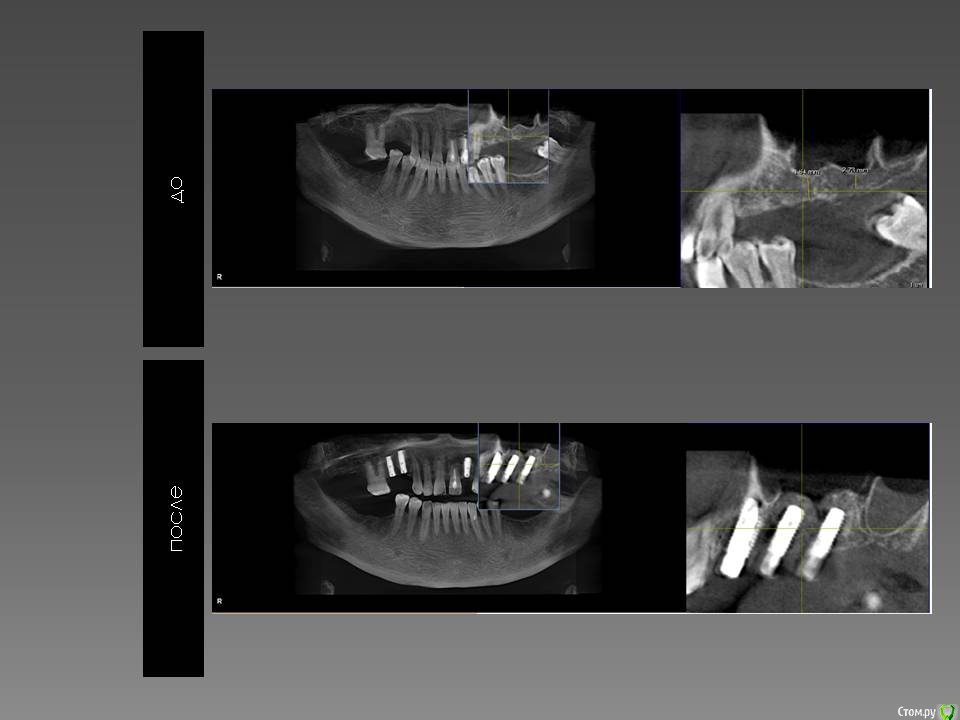

Доктор Добрых Дел Опубликовано 8 апреля, 2016 Поделиться Опубликовано 8 апреля, 2016 Мукотом разве не через "О" пишется?) Почему такой сильный медиальный наклон имплантатов? Или это на срезе так кажется? Ссылка на комментарий

K.E. Опубликовано 8 апреля, 2016 Поделиться Опубликовано 8 апреля, 2016 Позиция имплантатов хорошая на мой взгляд.Зачем делать открытый синус?Смущает мед. наклон. Ссылка на комментарий

Доктор Хаус Опубликовано 9 апреля, 2016 Поделиться Опубликовано 9 апреля, 2016 Здорова Роберт, а постановку делал ? Совмещал виртуальную модель с постановкой имплантов на кт? То же есть впечатление что медиально наклонил. Ссылка на комментарий